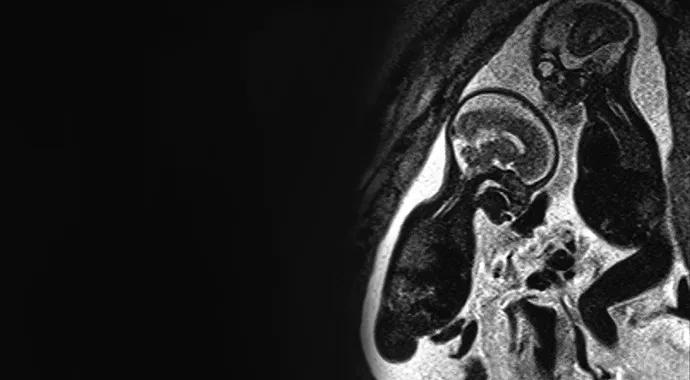

Figure 6. Lumbosacral myelomeningocele with type II Chiari malformation. Sagittal HASTE T2 image shows an open neural tube defect (myelomeningocele) extending from the midlumbar level down to involve the entire sacral region (arrows). Note small posterior fossa and low-lying cerebellar tonsils. Polyhydramnios and rocker bottom foot are also noted (open arrow).